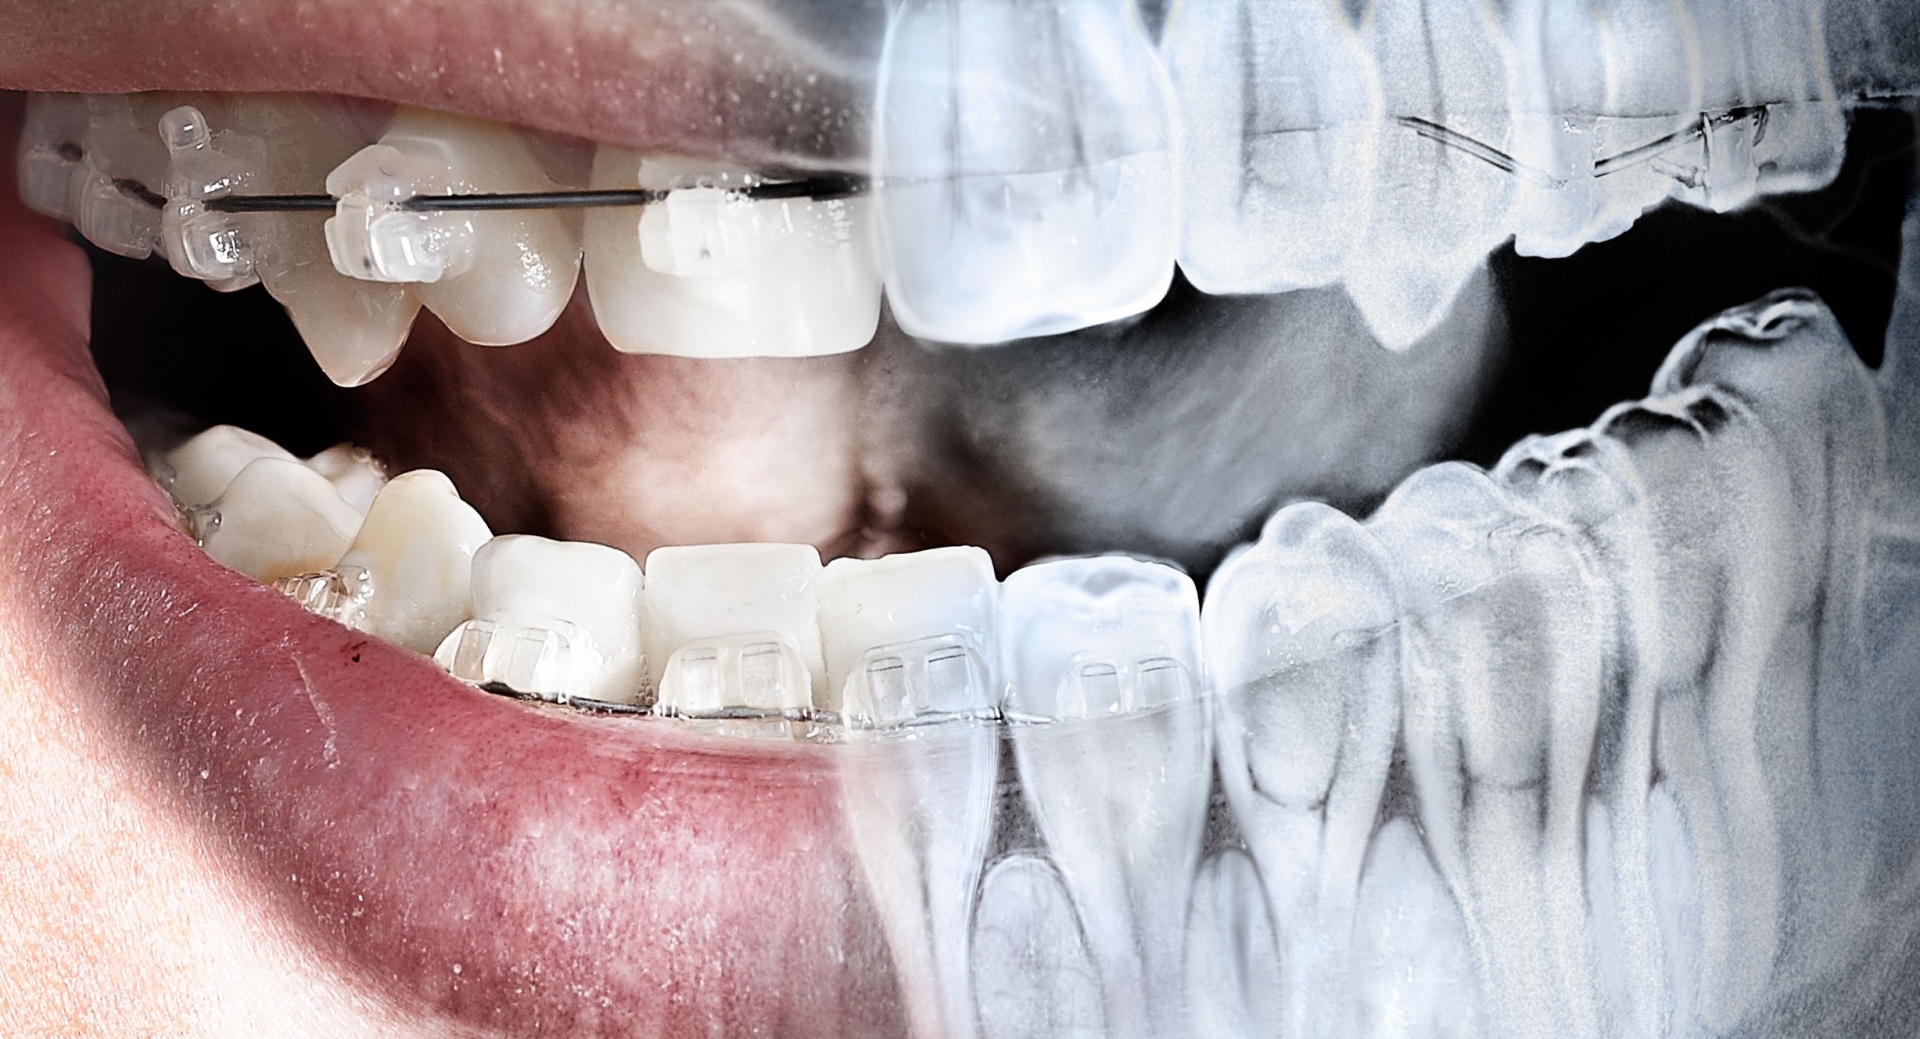

Fotografias Intra-Orais e Extra-Orais

ESCANEAMENTO INTRAORAL

Escanamento intraloral que elimina completamente a documentação física